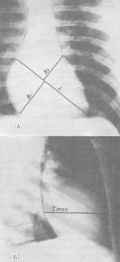

Рис. 15. Телерентгенограммы сердца: А — фронтальная проекция; Б — сагиттальная проекция; B1+B2 — "ширина"; L — длинник сердца; tmax — "глубина" сердца. |

О размерах спортивного сердца судят по данным телерентгенометрического исследования: производится два рентгеновских снимка во фронтальной и сагиттальной проекциях (рис. 15). Полученные рентгенограммы обрабатывает врач, который рассчитывает объем спортивного сердца (в см 3).